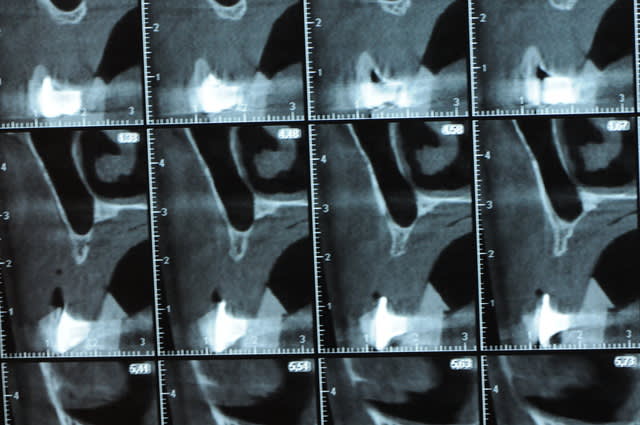

Une petite étude de ton cas D57

Sous réserves bien sur de voir l’animal en vrai

Les zones exploitables radiologiquement parlant:

Coupes implant

2,3 40100

4,96 35130 avec sinus lift mais difficile

5,25 35150

6,02 35130

6,78 35115 après réduction de hauteur de crête

7,26 35115 après réduction de hauteur de crête

8,51 35150

10,43 40115 ou 50115

11,10 40115

Ce qui nous fait 9 implants possible évidement avec un comblement de sinus on augmenterait encore les zones implantable mais ce n’est pas le but recherché, avec 8 (4+4) il doit être possible de faire une belle barre support de complet

Je n’ai pas eu le temps de te téléphoner, ça viendra